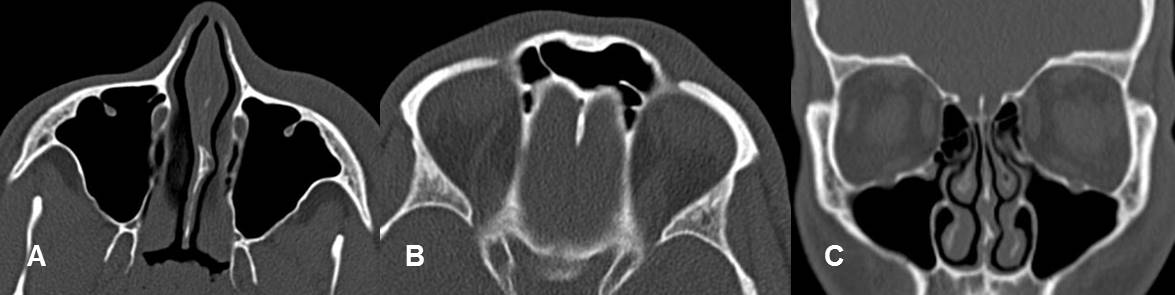

Fig 209. Orbita normal.

A y B: TAC axial. Piso y techo de las órbitas respectivamente.

C: TAC reconstrucción coronal. Rebordes orbitarios completos.

Fig 210. Orbita normal.

A: TAC axial y B: TAC reconstrucción coronal. Músculos recto interno (Flechas delgadas) y recto inferior (Flechas gruesas) normales. Ambos tienen forma ovalada.